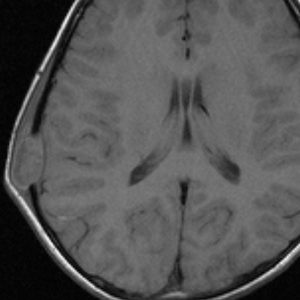

脳のLCH(ガドリニウム増強されるタイプ)

- 左の写真は,両側の側頭葉内側(黄色の矢印)と視床下部(赤)に同時にできたLCHです

- このように脳のLCHは近寄った場所に多発するように散在性に発生することがあります

- これを単発病変とするのか1臓器の多発病変とするのかはわかりません

- 左の写真は3ヶ月後のものですが,なにも治療しないで自然に病巣は消失してしまいました(自然寛解)

- しかし,脳のLCHは脳組織を破壊して広がりますから,病像が消えても症状は後遺症として残ることが多いです

- ですから,脳病変が発見されたら正確に診断して治療を行った方がいいでしょう